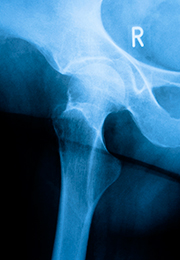

Aumento del riesgo de fracturas de cadera y vertebras

Estas fracturas, así como la fractura de cadera o la fractura de Colles (las más frecuentes) se presentan ante mínimos traumatismos o en algún caso, como hallazgo radiológico.